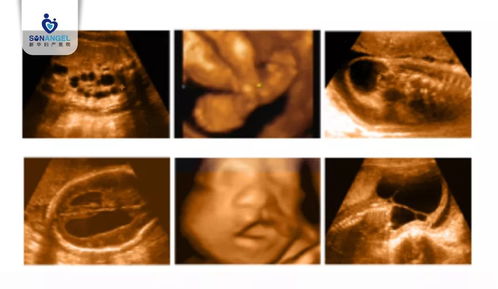

系统彩超,又称系统胎儿超声检查,是一种无创的医学影像检查方法,通过超声波成像技术对胎儿进行全面的检查。它可以帮助医生了解胎儿的生长发育情况,评估母体健康状况,并早期发现胎儿畸形、染色体异常等问题。

23周系统彩超的检查内容主要包括以下几个方面:

头部检查

观察颅骨、大脑、小脑、脑室等结构是否正常,排除脑积水、无脑儿等疾病。

颜面部检查

观察眼、鼻、口、唇等结构是否正常,排除唇腭裂等畸形。

心脏检查

观察心脏结构、血流情况,排除先天性心脏病等疾病。

腹部检查

观察肝脏、肾脏、胃、膀胱等器官是否正常,排除器官畸形等疾病。

四肢检查

观察四肢骨骼、肌肉等结构是否正常,排除肢体畸形等疾病。

胎盘、羊水、脐带检查

评估胎盘、羊水、脐带等母体情况,确保胎儿在宫内安全。